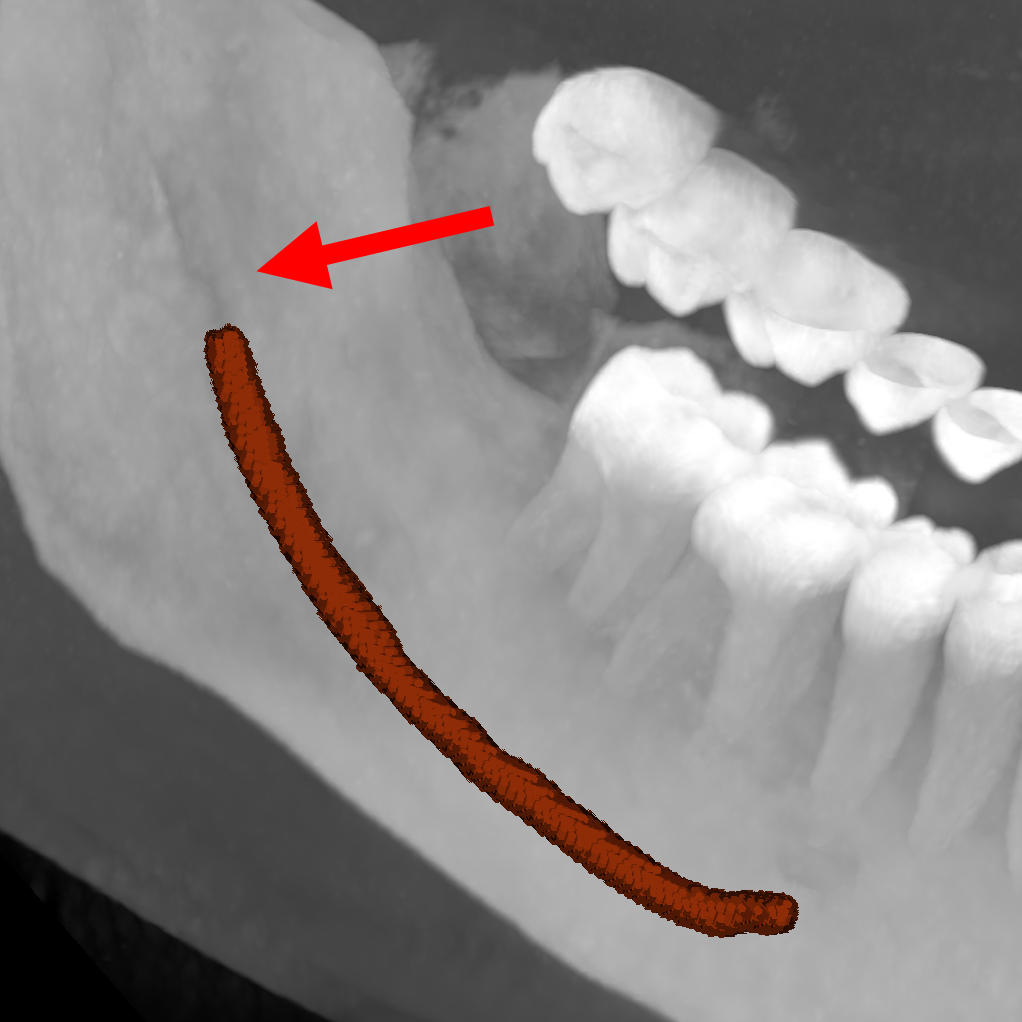

| ToothFairy[6, 5] | 3D | binary | 138 | Inferior Alveolar Canal |

We employ five public datasets featuring thin structures for validating the proposed Skeleton Recall Loss. The datasets span natural as well as medical images, covering a range of segmentation challenges, including both binary and multi-class segmentation problems in 2D as well as 3D contexts. An overview of the datasets can be found in Tab. 1. Among the three 2D datasets used in this study, the Digital Retinal Images for Vessel Extraction (DRIVE) dataset [32] was employed, focusing on retinal vessel segmentation. Additionally, structural inspection images designed for concrete crack segmentation (Cracks) [36] and aerial images of Massachusetts for road segmentation (Roads) [21] were included, highlighting the diversity of thin structures in natural and constructed environments. In the 3D domain, we incorporated two cutting-edge medical image segmentation challenge datasets. One of them was ToothFairy111https://toothfairy.grand-challenge.org/, which was a segmentation challenge on 3D Cone-Beam CTs [6, 5] featuring the inferior alveolar canal as the target structure. Additionally, the TopCoW222https://topcow23.grand-challenge.org/ dataset for topology-aware 3D segmentation of vessels in the Circle of Willis for CTA and MRA data [40] was utilized, encompassing binary as well as multi-class segmentation on 13 different subtypes of vessels. This diverse set of datasets enables a comprehensive evaluation of the proposed Skeleton Recall Loss, demonstrating generalizability of the method to a wide range of thin structure segmentation challenges in both 2D and 3D contexts.